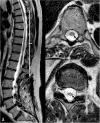

Background: Vascular lesions of the spinal cord are rare but potentially devastating conditions whose accurate recognition critically determines the clinical outcome. Several conditions lead to myelopathy due to either arterial ischemia, venous congestion or bleeding within the cord. The clinical presentation varies, according with the different aetiology and mechanism of damage.

Purpose: The aim is to provide a comprehensive review on the radiological features of the most common vascular myelopathies, passing through the knowledge of the vascular spinal anatomy and the clinical aspects of the different aetiologies, which is crucial to promptly address the diagnosis and the radiological assessment.